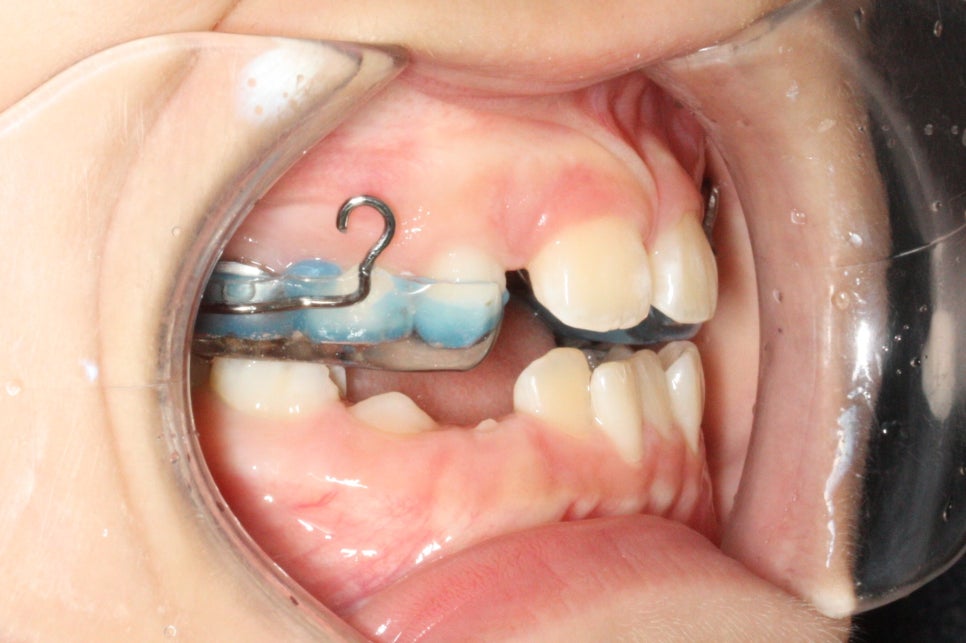

골격적 문제해결보다는 치성효과를 더 크게 하기 위한 #페이스마스크 치료를 6개월 진행하였습니다.

이후 비대칭 치료도 진행하며 다양한 장치들을 약 3년간 적절히 사용하였습니다.